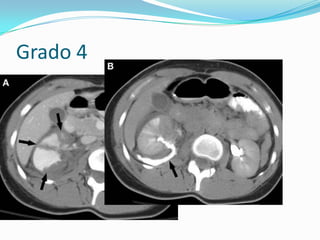

Grado 4:laceracion vía y extravasación

Grado 4

Grado 4:laceracion víay extravasación